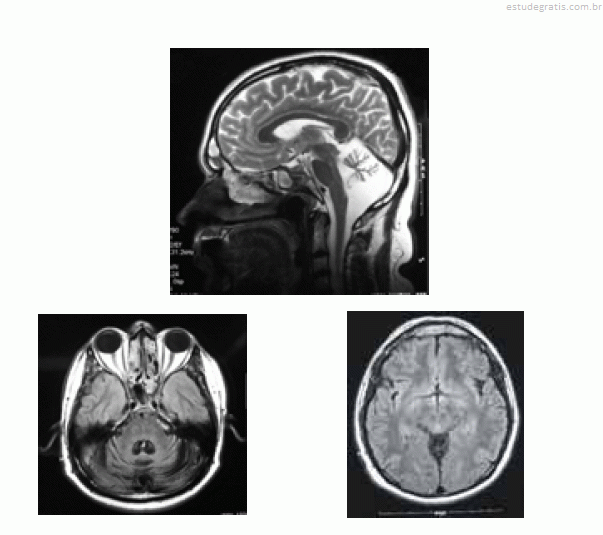

José, com 42 anos de idade, foi renovar sua carteira de motorista e, ainda na entrada do consultório, o médico observou uma marcha com base alargada e insegura. Durante a avaliação clínica, ao testar a coordenação, o médico verificou tremor de intenção à prova índex-nariz, dismetria e disdiacocinesia bilateral. Os pares cranianos, a força muscular e os reflexos — profundos e superficiais — eram normais. A fala de José era pausada, silabada. Ao ser questionado sobre o uso de álcool, negou-o e referiu que o problema do desequilíbrio vem piorando nos últimos dez anos, fato que provocou o acompanhamento médico e motivou a realização de uma ressonância nuclear magnética (RNM), cujas imagens são apresentadas abaixo.